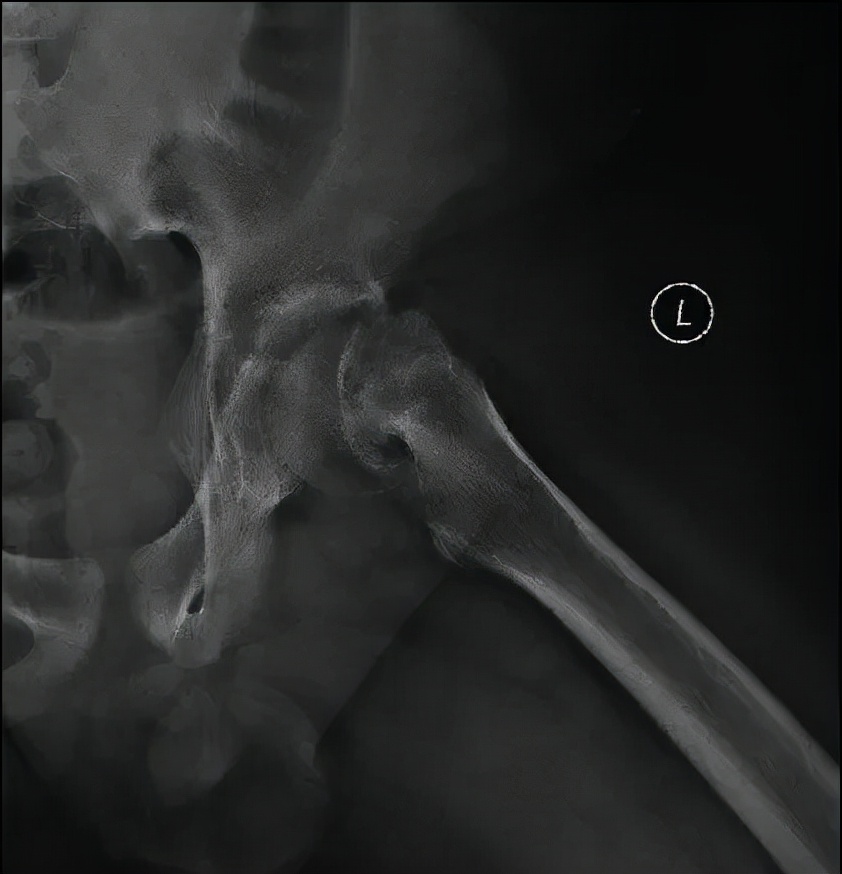

病例1 男,13岁,左侧重度SCFE

病例1 髋关节外科脱位,改良Dunn截骨,术后2年,X线示位置良好,无股骨头缺血坏死